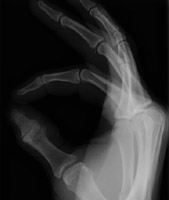

Volar plate fractures are the result of hyperextension. This injury typically involve the proximal interphalangeal joint of the fingers. At this location, the volar plate (a dense fibrous band) forms a portion of the capsule. Typically, there is a small fragment of bone avulsed from the volar aspect of the base of the proximal phalanx. If not repaired, this can lead to instability. A Wilson fracture refers to a volar plate injury to the middle phalanx of a finger.

- Click on the image for a larger versionALateral radiograph of the hand. This shows an avulsion fracture of the base of the middle phalanx of the third digit.